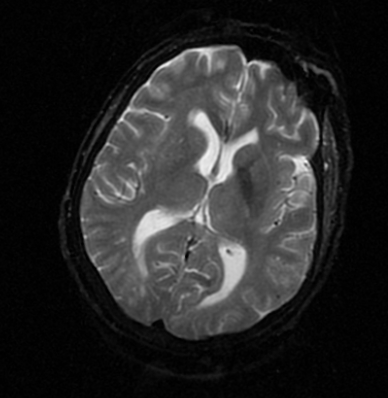

In this study, we aim to initiate the development of Radiology Foundation Model, termed as RadFM.We consider the construction of foundational models from the perspectives of data, model design, and evaluation thoroughly. Our contribution can be concluded as follows: (i), we construct a large-scale Medical Multi-modal Dataset, MedMD, consisting of 16M 2D and 3D medical scans. To the best of our knowledge, this is the first multi-modal dataset containing 3D medical scans. (ii), We propose an architecture that enables visually conditioned generative pre-training, allowing for the integration of text input interleaved with 2D or 3D medical scans to generate response for diverse radiologic tasks. The model was initially pre-trained on MedMD and subsequently domain-specific fine-tuned on RadMD, a radiologic cleaned version of MedMD, containing 3M radiologic visual-language pairs. (iii), we propose a new evaluation benchmark that comprises five tasks, aiming to comprehensively assess the capability of foundation models in handling practical clinical problems. Our experimental results confirm that RadFM significantly outperforms existing multi-modal foundation models. The codes, data, and model checkpoint will all be made publicly available to promote further research and development in the field.